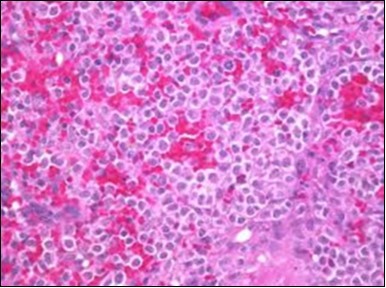

Figure 6.HCL: disseminated hairy cells with a clear cytoplasm(22).

The leukaemia cells may enunciate a characteristic immune phenotype, crucial for a confirmatory diagnosis. The peripheral blood mononuclear B cell population may display a kappa or lambda light chain restriction. The phenotype of classic hairy cell leukaemia may be delineated by concurrent, immune reactive CD19+ CD20+,CD 11c+, CD25+, CD103+ and CD123+. An intensely immune reactive CD200+ and a non reactive CD27- antigen may be present2, 4. Evaluation of a trephine bone marrow biopsy and bone marrow aspirate may define the degree of tumour infiltration. A dry tap on account of prominent bone marrow fibrosis may be elucidated at preliminary diagnosis. A decline in the normal haematopoiesis may account for a hypo-cellular marrow in 10% instances. Gradation of cellular infiltrating of the leukaemia within the bone marrow may be appropriately investigated with immune –histochemical stains2, 4. Immune staining for CD20+, annexin 1 and VE1 (a BRAF V600E stain] may validate the diagnosis and precisely analyse the extent of malignant bone marrow infiltration[8]. Determination of BRAF V600E mutation may be critical in therapeutically non responsive individuals with applicable standard therapy or in instances of multitudinous reoccurrences[9]. Deploying inhibitors of BRAF V600E gene may be efficacious in patients impervious to approved therapy. The mutation necessitates a comprehensive scrutiny of the implicated individuals with a sensitive molecular assay which may discern up to < 10% of the hairy leukaemia cells appearing in the peripheral blood smears or bone marrow aspirates diluted with peripheral blood or aspirates elucidating a dry tap[2,4]. Allele specific polymerase chain reaction (PCR) or a next generation sequencing may be optimally employed to circumvent false negative outcomes. If the leukaemia cells are sparse or if particularly sensitive & efficacious molecular techniques are not accessible, the application of appropriate immune histochemical stains to the bone marrow biopsy such as a BRAF V600E mutation stain (VE1) may detect the hairy cells and conclusively diagnose the condition[2,4,10]. Figure 1, Figure 2, Figure 3, Figure 4, Figure 5, Figure 6, Figure 7, Figure 8, Figure 9, Figure 10, Figure 11, Figure 12, Figure 13, Figure 14.